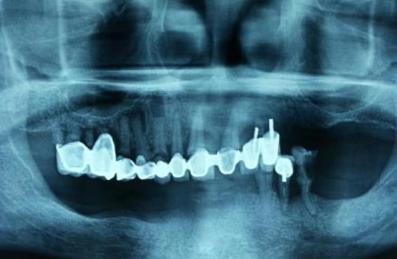

很多做过美容冠的患者在后期因为出现各种问题而拆除冠后,常常可以看到剩余的牙齿和牙周组织惨不忍睹,严重的甚至无法保留而只能拔除。

以下是做过“美容冠”患者的患者牙齿,触目惊心啊~

@西安牙医老聂:说中无所不能的“美容冠”!

@佳头2011:患者烤瓷修复四年,美容冠